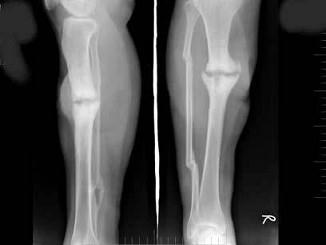

问题 女,48岁,车祸致右胫腓骨骨折,外固定术后两年复查,如图所示,最可能的诊断是?(?)

选项 A.右胫骨愈合延迟 B.右胫骨假关节形成 C.右胫骨骨折愈合好,有大量骨痂形成 D.右胫骨断端不连 E.以上均不正确

答案 A